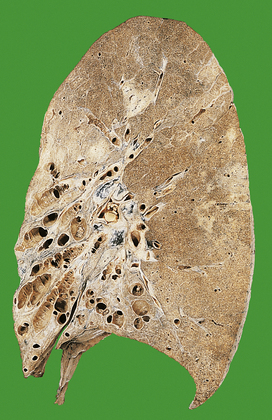

Fungi

Both Candida and Aspergillus species can cause widespread areas of necrosis (Fig. 14.9). Micro-abscesses contain the characteristic fungal filaments (hyphae).

image

Fig. 14.9 Aspergillus pneumonia. Lung at autopsy showing focal yellow areas of consolidation.